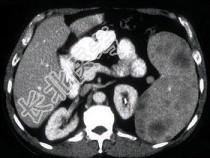

- 单项选择题患者中年,结合图像, 最不可能的诊断为 ( )

A、Gauchers 病(家族性脾性贫血)

B、淋巴瘤

C、转移性黑色素瘤

D、镰刀形红细胞病

E、以上都不是